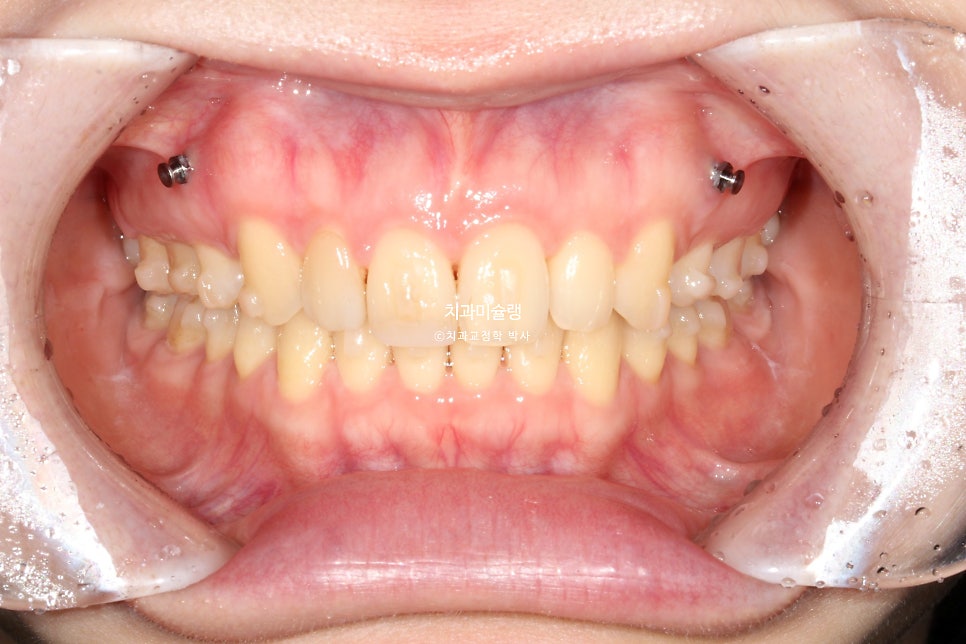

환자 초진 상태

2023년 4월 초진

23년 4월, 교정치료를 위해 오신 20대후반 환자입니다. 실제론 앞니가 전반적으로 작은편임에도 불구하고 사진에서 앞니가 유독 커보이는건 돌출되어있기 때문입니다.

치열은 정면에서 볼때 원근법을 따르기에 튀어나와있으면 커보이고 뒤로갈수록 작아보이죠.

예전에 앞니를 다쳐서 부러진적이 있어 레진으로 치료해놓은 상태입니다.

외상이력이 있는 치아는 교정중 드물게 뼈와 붙어 이동하지 않는 유착 현상이 일어나기에 모니터링을 잘 해야합니다.

앞니 2개가 유난히 돌출되어 있습니다.

앞니뿐 아니라 어금니 교합관계가 2급입니다.

악궁이 좁고 뾰족합니다.

한쪽 사랑니가 깨끗하게 잘 나와있습니다. 반대쪽 사랑니도 곧 내려오겠죠.